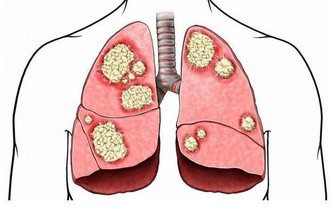

目前風行的鐳射近視手術,其實並沒有真正解決近視的問題,只是治標不治本,充其量只是讓我們不用戴眼鏡也可以看得清楚而已。對於原本因近視而變長的眼軸,無法靠鐳射近視手術回復原狀,因此近視所造成的並發症不但無法減少,甚至有些學者還認為可能會增加並發症的風險。

近視患者要戴眼鏡(凹透鏡)才能看清楚,原理是利用凹透鏡將光線往後曲折,讓光線可以聚焦到較長眼球的視網膜上,戴隱形眼鏡也是同樣的道理。鐳射近視手術的原理,是利用雷射光在眼角膜表面做磨平處理,使得磨平後的眼角膜能將折射的光線更往後曲折,而聚焦到變長眼軸的視網膜上,免除戴眼鏡的麻煩。

這種近視手術只是一種表面的美容手術,無法防治近視可能產生的諸多並發症。所以我才一再強調,身為父母,對兒童近視不能放任不管,一旦讓孩子變成高度近視者就後悔莫及了。